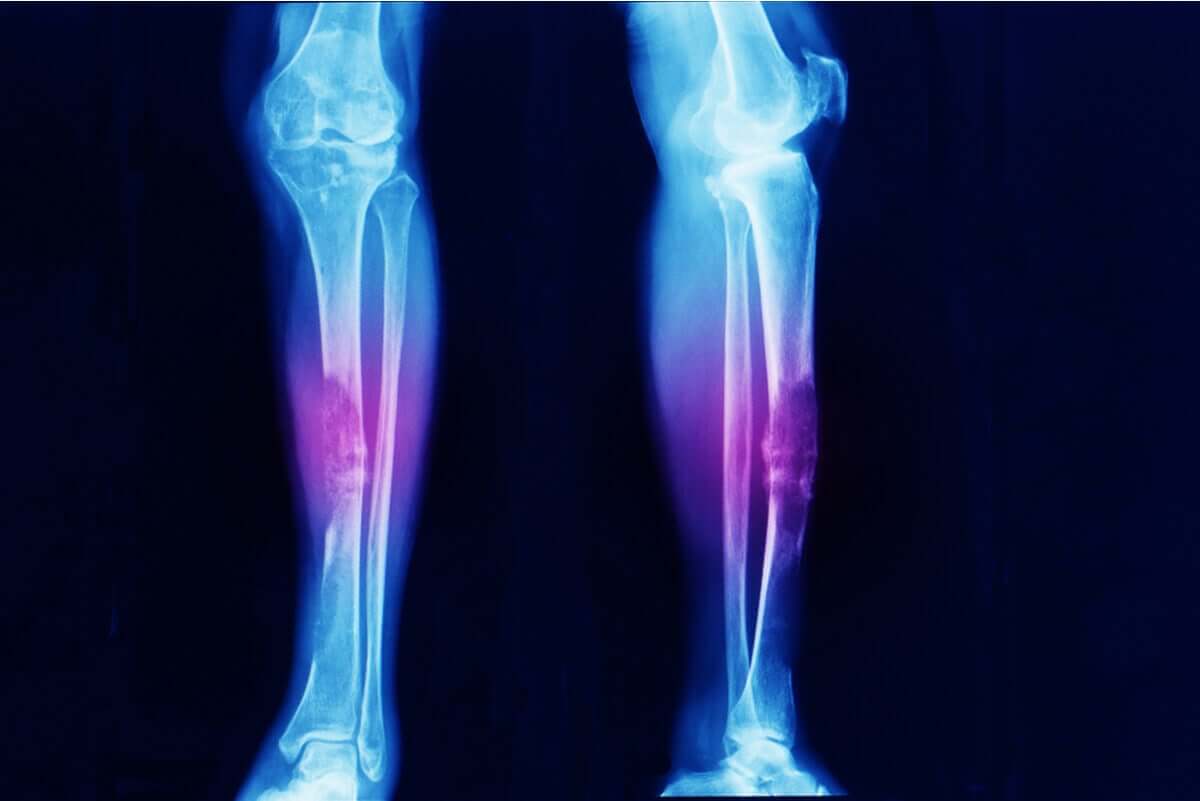

- Mięsak kości: obejmuje tkankę kostną.

Mięsak to nowotwór dotykający tkanek miękkich i tkanki kostnej. Objawy zależą od umiejscowienia guza.